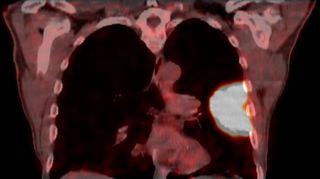

Lungenkrebs

Lungenkrebs befällt etwa 25 Prozent aller Krebskranken und gilt als häufigster Tumor beim Mann. Doch auch immer mehr Frauen sind betroffen. Die chirurgische Therapie ist für uns Mittel der Wahl, sofern keine Fernmetastasen vorhanden sind. Dabei können wir in unserer Klinik technisch hoch anspruchsvolle Lungenoperationen auf endoskopische Weise videoassistiert vorgenommen werden.

Mit dem Begriff "minimal-invasive Thoraxchirurgie" werden Schlüsselloch-Techniken für Operationen bezeichnet, in der Thoraxchirurgie eine noch junge Methode, die sich rasant entwickelt. In unserer Klinik kann diese schonende Technik sogar bei der Therapie von Lungenkrebs zum Einsatz kommen.

Technisch hoch anspruchsvolle Lungenoperationen können in unserer Klinik auf endoskopische Weise videoassistiert vorgenommen werden (VATS: Video-assistierte Thoraxchirurgie). Die bei konventionellen Lungenoperationen notwendige Eröffnung des Brustkorbs mit einem großen Schnitt und mit Auseinanderspreizen der Rippen entfällt bei der VATS-Lobektomie. Die Patienten erholen sich wegen der sehr viel geringeren Wunde („Operationstrauma“) sehr viel schneller. Auch sind die durch die Operation hervorgerufenen Schmerzen deutlich geringer. Bei einer anatomischen Operation mit Lungenteilentfernung müssen die „Versorgungsleitungen“ durchtrennt werden, dies sind die Blutgefäße und die Luftröhrenäste. Diese Operationsschritte und mehr können endoskopisch vorgenommen und über Video-Übertragung am Monitor mit Vergrößerung durchgeführt werden. Die Technik der VATS–Lobektomie/Lappen-Resektion wird bei Frühstadien des Lungenkrebses erfolgreich eingesetzt wie auch bei einer Vielzahl anderer anatomischer Lungenoperationen (Segmentresektionen).

Lungenmetastasen

Werden neben Lungenkrebs auch Lungenmetastasen diagnostiziert, stellt das die Medizin vor höchste Herausforderungen. Nur wenige Kliniken sind darauf spezialisiert, bei dieser Erkrankung chirurgisch einzugreifen. Durch besondere fachliche Expertise, einen großen Erfahrungsschatz und die technische Ausstattung ist unsere Klinik Ihr Ansprechpartner, wenn es um die chirurgische Therapie von Lungenmetastasen geht.

Laser-Chirurgie bei Lungenmetastasen

In unserer Klinik für Thoraxchirurgie werden zahlreiche Operationen an der Lunge mit dem modernen 1318NM-Diodenlaser durchgeführt. Das neue Gerät wurde speziell für die Lungenchirurgie entwickelt und hat besondere Eigenschaften, die das Schneiden von Lungengewebe ermöglichen: Mit dem Laser ist der Thoraxchirurg in der Lage, bluttrocken und übersichtlich durch das Lungengewebe zu schneiden. Dadurch können Metastasen und Tumoren, die tief im Lungengewebe liegen, onkologisch sicher entfernt werden. Anhand dieses modernen Verfahrens kann der Thoraxchirurg besonders gewebeschonend vorgehen und zahlreiche Lungenmetastasen entfernen, was mit konventionellen Methoden nicht möglich wäre. So kann die Prognose für den Patienten verbessert werden. Die sogenannte Laser-Metastasektomie ist eine etablierte chirurgische Behandlung, die bundesweit nur in großen Thoraxkliniken vorgenommen wird. Unsere Klinik ist die einzige in Ostwestfalen-Lippe, die Laser-Chirurgie bei Operationen der Lunge anbietet.